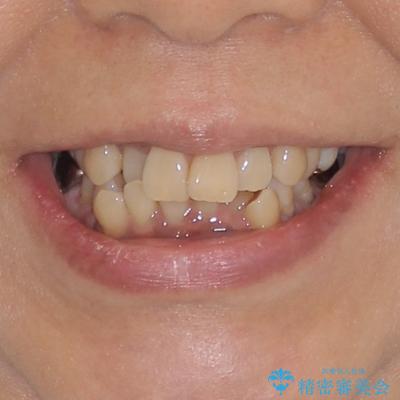

- 八重歯やクロスバイトを気にして来院された患者様です。

口元の突出感はありませんでしたが、デコボコが強く、非抜歯矯正とすると出っ歯仕上がりとなる可能性があったため、上下左右の第一小臼歯4本を抜歯し、ワイヤー装置にて矯正治療を行うこととしました。